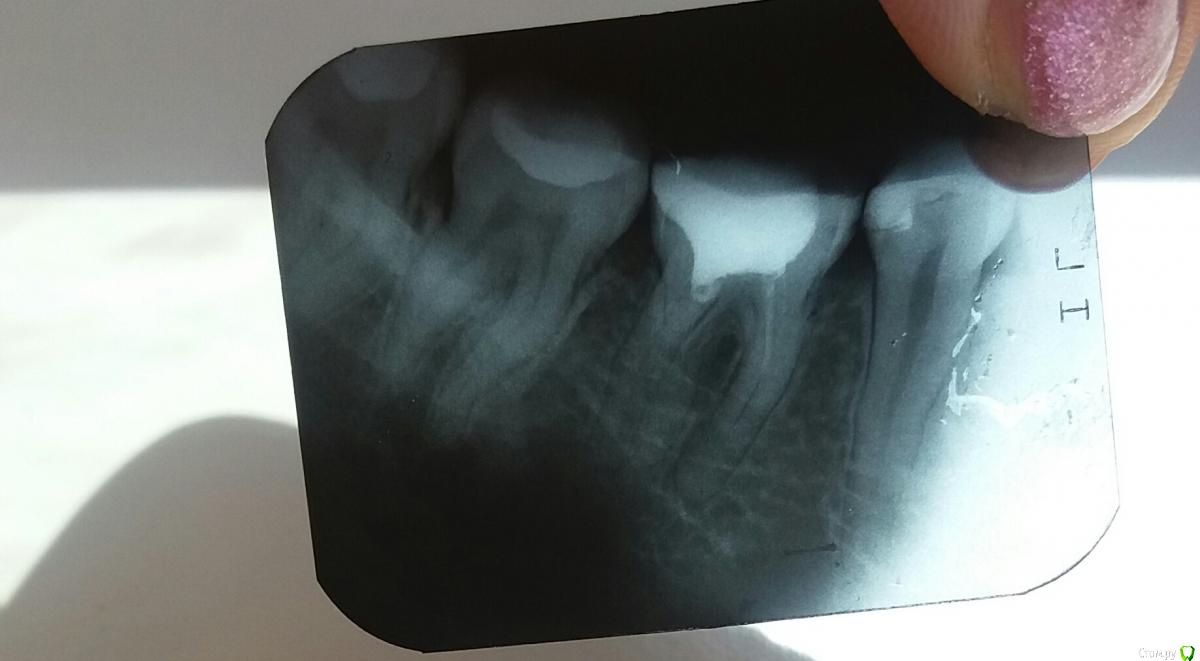

Анна Л Опубликовано 2 мая, 2018 Поделиться Опубликовано 2 мая, 2018 (изменено) Первый раз в 2016 году лечили мне зуб с пломбировкой каналов. Снимок номер 1. Неделю назад переплобмировали мне каналы, врач оставила там интсрумент. Снимок тоже прилагаю. Направила к доктору лечить под микроскопом. Он не смог достать интсрумент и сказал что не прошел все каналы, это невозможно и сделал все что мог и залил каналы горячей гуттаперча и врменной пломбой. Через 3 для пошла на процедуру подгтовие вкладки, снова временная пломба. И вот на след день у меня начал ныть зуб,температура 37, немного опухла щека, ночью сплю зуб не беспокоит, а вот днем все та же ноющая боль и боль как будто до уха доходит. Пью третий день порошок Нимесил, 2 раза в сутки. Боль моя и не увеличивается и не ументшается. Врач говорит дальше пить Нимесил.Первый раз в 2016 году лечили мне зуб с пломбировкой каналов. Снимок номер 1. Неделю назад переплобмировали мне каналы, врач оставила там интсрумент. Снимок тоже прилагаю. Направила к доктору лечить под микроскопом. Он не смог достать интсрумент и сказал что не прошел все каналы, это невозможно и сделал все что мог и залил каналы горячей гуттаперча и врменной пломбой. Через 3 для пошла на процедуру подгтовие вкладки, снова временная пломба. И вот на след день у меня начал ныть зуб,температура 37, немного опухла щека, ночью сплю зуб не беспокоит, а вот днем все та же ноющая боль и боль как будто до уха доходит. Пью третий день порошок Нимесил, 2 раза в сутки. Боль моя и не увеличивается и не ументшается. Врач говорит дальше пить Нимесил. Изменено 2 мая, 2018 пользователем Анна Л Ссылка на комментарий